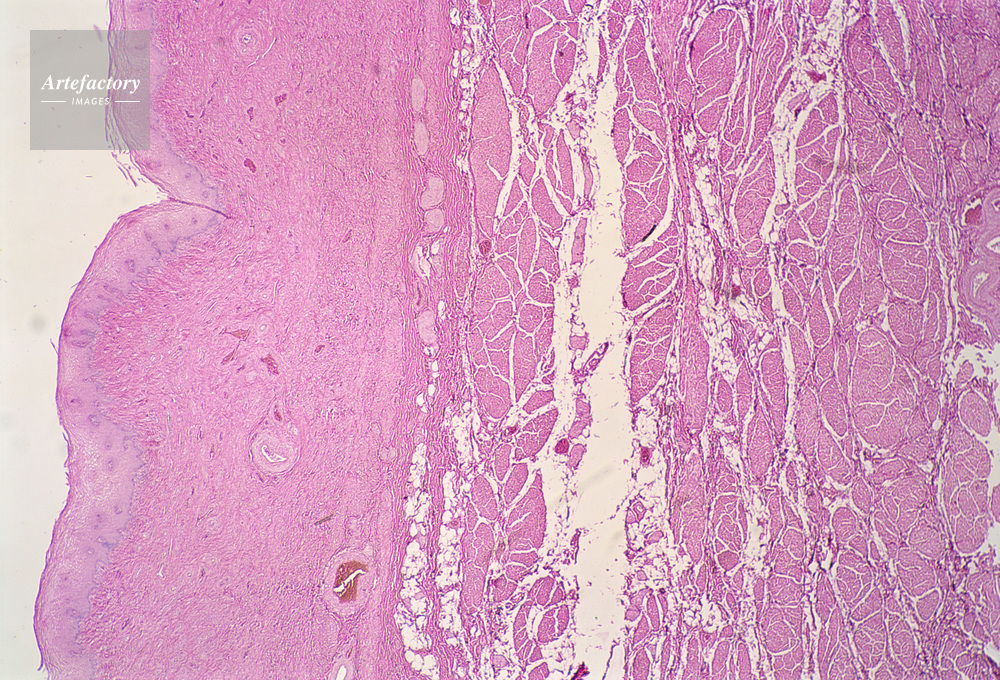

| キャプション | 膣,人間,10倍, | 制限事項 | ||